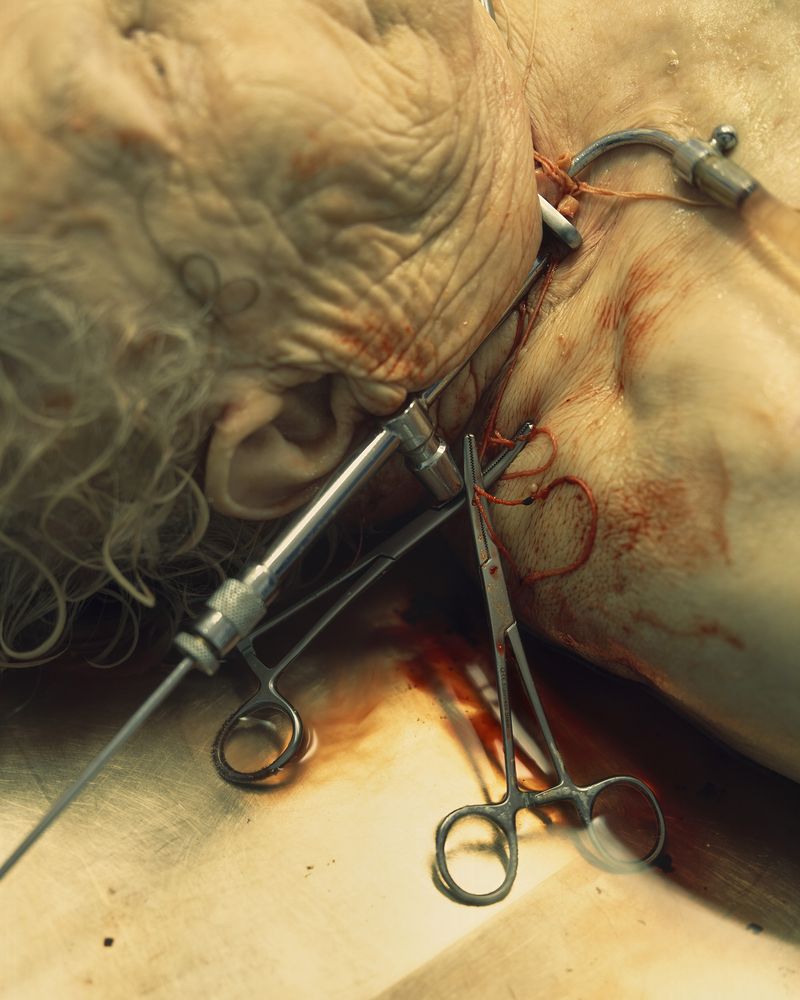

My work asks questions and challenges contemporary social and cultural attitudes towards the perception of death, the quality of life, reflections on the essence of humanity on philosophical and technological grounds. The story of our corporeality aims to begin a discourse about what has been tabooed or is socially marginalized:

medical bioengineering, technology in medical service, change in the perception of a dead body and the aspect of loss. Such a discourse could reveal the needs and solutions for the development of bioengineering in Poland. The increasingly appearing idea of transhumanism in this aspect considers dysfunctional elements of the human condition, such as disability, suffering, disease and ageing, to be undesirable, often still remaining only an idea but also a goal.

Modern, diminishing contact with death, a culture based on the endless need for youth, its improvement, resisting death through science, strongly intensifies the fear of dealing with the subject of death in everyday life. In the XIX and early XX-centuries, post-mortem photography was very popular, due to several reasons of the more frequent presence of death in everyday life, as well as its absence in photography, people did not have too many such photos, and post-mortem photography is the last moment to paradoxically, keep the memories alive. It has in itself attributes of simultaneous passing and keeping away from the loss, preservation of consciousness for an indefinite period of time.